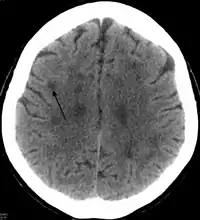

In HDLS, there is enlargement of the lateral ventricles and marked thinning or weakening of cerebral white matter.[6] The loss of white matter is caused by myelin loss. These changes are associated with diffuse gliosis, moderate loss of axons and many axonal spheroids.[1]

Standard MRI scans have been performed on 1.5 Tesla scanners with 5 mm thickness and 5 mm spacing to screen for white matter lesions in identified families. If signal intensities of the MRI scans are higher in white matter regions than in grey matter regions, the patient is considered to be at risk for HDLS, although a number of other disorders can also produce white matter changes and the findings are not diagnostic without genetic testing or pathologic confirmation.[2]